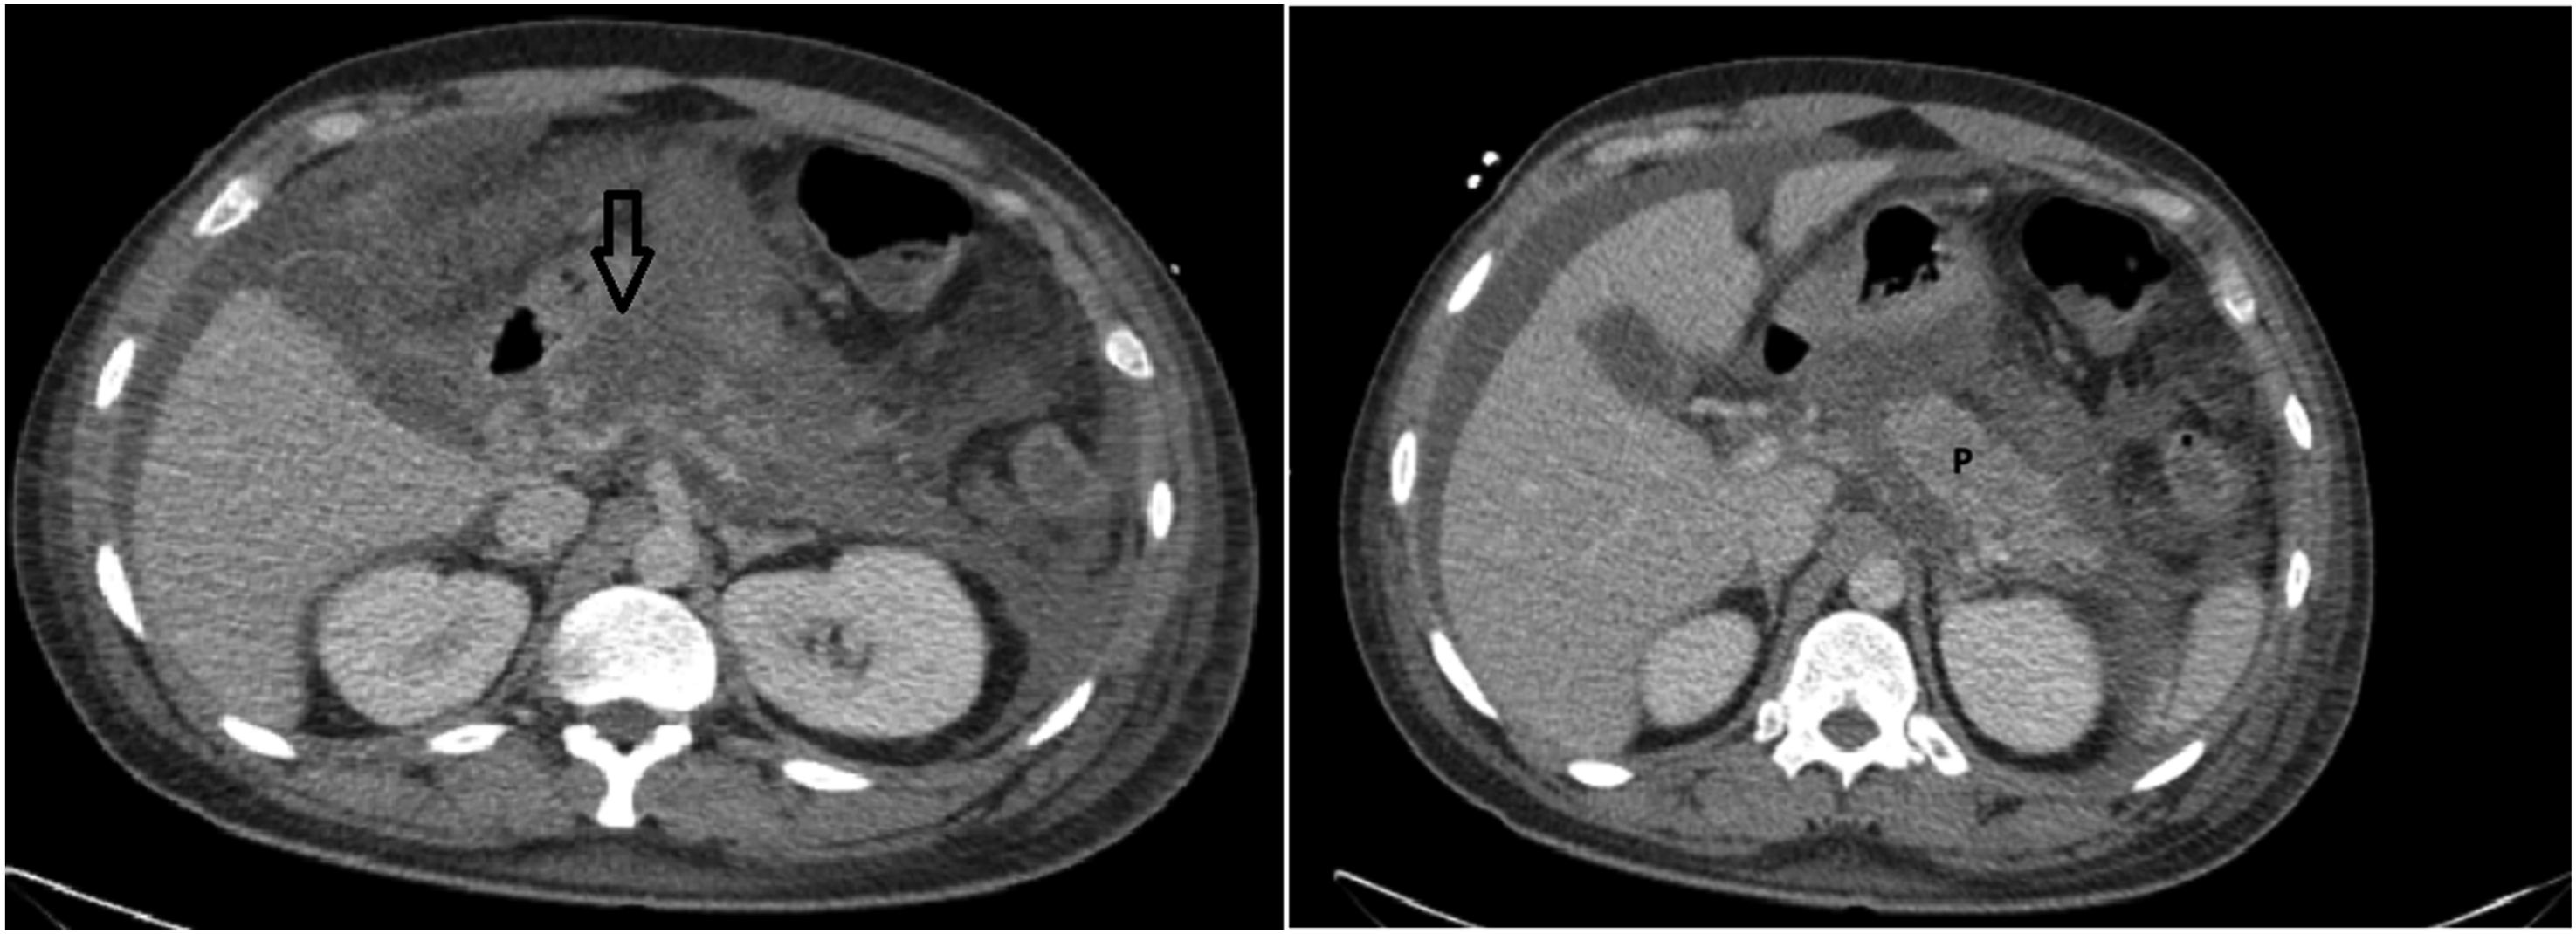

One month later, the patient was readmitted with recurrent abdominal pain, vomiting, fever, and worsening joint symptoms. Examination revealed multiple tender, erythematous subcutaneous nodules over both shins. Serum lipase was markedly elevated (15,000 U/L). Repeat CT of the abdomen revealed extensive pancreatic necrosis with peripancreatic fluid collections (Figure 4). Axial contrast–enhanced CT abdomen demonstrating pancreatic head necrosis (arrow), bulky pancreatic body (P), peripancreatic fluid and ascites.